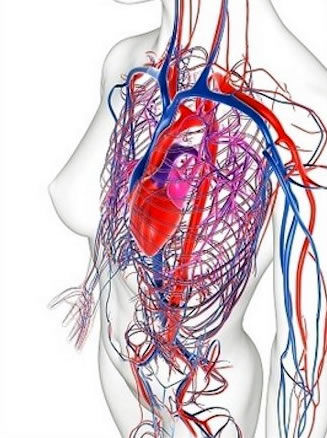

3. Aparato cardiovascular

1. Corazón

1. Gasto cardíaco

1. Embarazo avanzado

2. Circulación y presión arterial

1. Hipotensión supina

1. Renina, angiotensina II y volumen plasmático

1. Péptidos natriuréticos auriculares

1. Prostaglandinas

1. Endotelina

1. Óxido nítrico